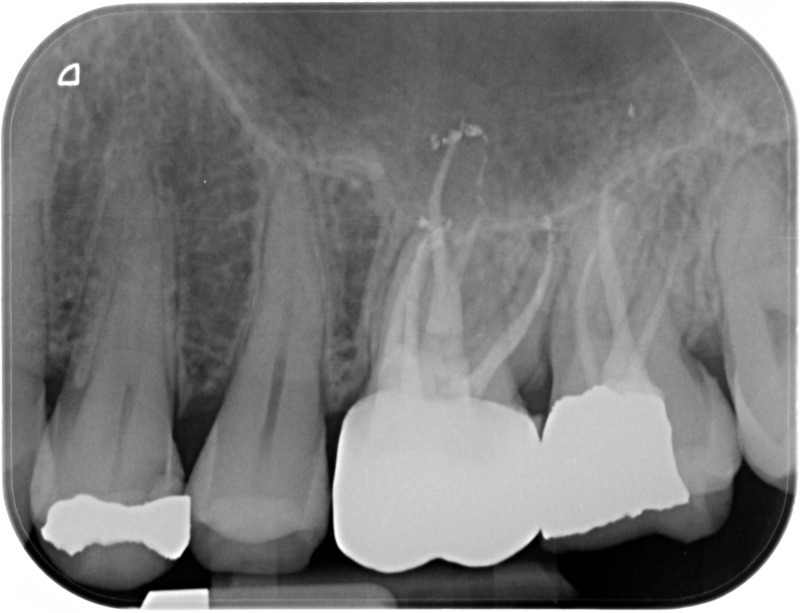

• Reprise de traitement endodontique : La manœuvre consiste à retourner à l’intérieur des racines d’une dent déjà traitée. Il arrive occasionnellement qu’une nouvelle inflammation se déclare suite à une reprise de carie ou une fracture de la dent, ou si le premier traitement endodontique est incomplet. Après s’être assuré que la dent lésée était conservable, il convient de désinfecter de nouveau le réseau canalaire parfois très complexe. La nouvelle obturation des canaux devra être protégée aussi rapidement que possible pour éviter une éventuelle contamination bactérienne.

Après